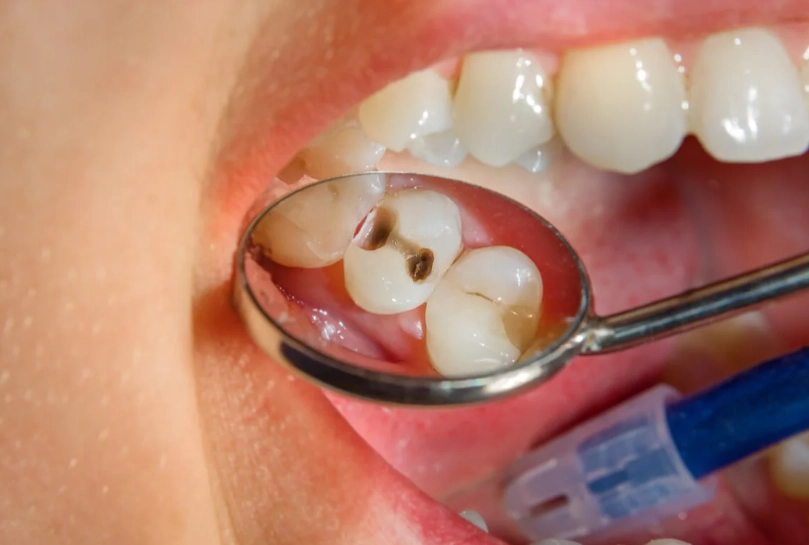

So, what exactly are we dealing with? In simple terms, a dental abscess is a localized collection of pus caused by a bacterial infection. Think of it as a boil, but inside your tooth or gums. This pus-filled pocket creates pressure, and since it's in a confined space (your jaw), that pressure translates directly into pain. The bacteria usually get in through a cavity, a crack in the tooth, or advanced gum disease.

It's also helpful to know there are different types, which start in different places. A periapical abscess happens at the very tip of the tooth's root, usually from an untreated cavity or trauma that lets bacteria infect the pulp (the tooth's nerve center). A periodontal abscess starts in the supporting bone and gum tissues next to the tooth root, often from advanced gum disease. The treatment approach can differ slightly based on the type.

But the real work is long-term prevention. A tooth abscess is almost always the result of a problem that was ignored. So, your new dental defense plan should be airtight.

- Fix Problems Early: That tiny cavity? Get it filled now. Don't wait for it to become a big, painful problem.